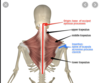

trapezius muscle location

attachments of trapezius muscle

Actions of trapezius muscle

anatomical relationships of trapezius muscle